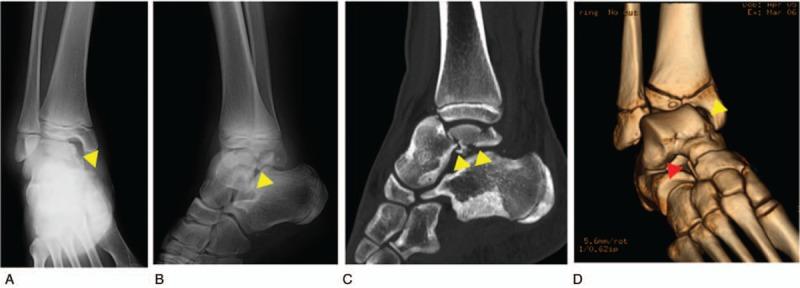

A 14-year-old boy was referred to our hospital owing to foot injury sustained on jumping off about 10 stairs.

Highly displaced talus body fracture of the dome and the posterior process.

Because the Linhart classification of this case was III-C and instability at the fracture site persisted even after closed reduction, we performed arthroscopic-assisted reduction and internal fixation (ARIF) using headless screws and an external fixator under general anesthesia.